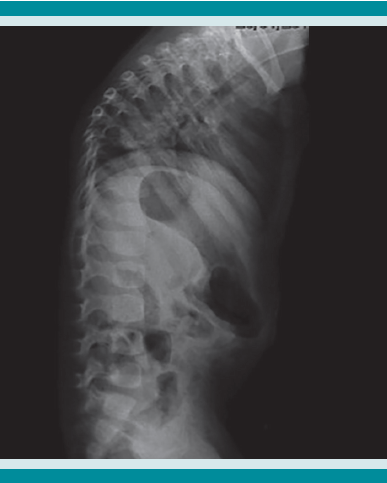

Paciente masculino de 2 años 3 meses, sin antecedentes heredo familiares ni patológicos de interés. El padecimiento se inició en septiembre de 2011 caracterizado por dolor de tipo mecánico en la región torácica posterior, de intensidad leve, pero con aumento con la actividad física, fiebre de 38 ºC, que se controló con acetaminofén. Cuatro semanas después tuvo irradiación de dolor hacia la cintura escapular derecha, con lateralización del cuello hacia el mismo lado. Refirió múltiples caídas desde un plano de sustentación ocasionadas por la disminución de la fuerza en las extremidades inferiores; además experimentó aumento de la cifosis torácica y falla de medro4.

A su ingreso al Instituto Nacional de Pediatría se llevó a cabo el protocolo multidisciplinario hospitalario, que incluye la revisión por parte de los especialistas en oncología, radiología, ortopedia e infectología. En los estudios de imagen se evidenció una lesión anterior a los cuerpos vertebrales de T7-T8 de características líquidas y reforzamiento en la periferia, con destrucción de los cuerpos vertebrales de T7 y T8 a expensas del colapso vertebral que desplaza la médula espinal, con primera posibilidad diagnóstica de tipo infecciosa (espondilodiscitis). Se inició el protocolo de estudio.

El resto de las pruebas de laboratorio son inespecíficas; hay aumento de la velocidad de sedimentación globular y proteína C reactiva y leucocitosis. Los estudios de imagen que se solicitan son: radiografía de tórax, que puede mostrar cambios dependiendo de la fase en la que se encuentre la enfermedad. Los cambios incluyen desde linfadenopatía en la tuberculosis inicial hasta un fino sombreado reticular en la tuberculosis hematógena o miliar. Las lesiones cavitarias son más frecuentes en pacientes adolescentes y adultos como reactivación de la infección latente pulmonar.

La tomografía axial computada de alta resolución puede demostrar lesiones de la primoinfección o linfadenopatía, aun cuando la radiografía de tórax se reporte normal.13 La resonancia magnética se utiliza en mayor medida para la tuberculosis músculo esquelética y de tejidos blandos y, como en este caso, para diferenciar una tumoración de un granuloma en la columna vertebral.14 Otros métodos, como la gammagrafía, que con marcadores como Tecnecio 99 tiene una especificidad de 30% y con galio de 70%. El SPECT y PET tienen mejor especificidad que la tomografía o gammagrafía para discernir entre tuberculosis y lesiones cancerosas,15 con un valor predictivo negativo mayor de 90%, a diferencia de pacientes con tuberculosis pulmonar, además de mayor captación e identificación de lesiones óseas se puede utilizar como auxiliar en tuberculosis extrapulmonar. Finalmente, pueden ser de gran ayuda para determinar el grado de actividad de la enfermedad y la respuesta al tratamiento indicado.